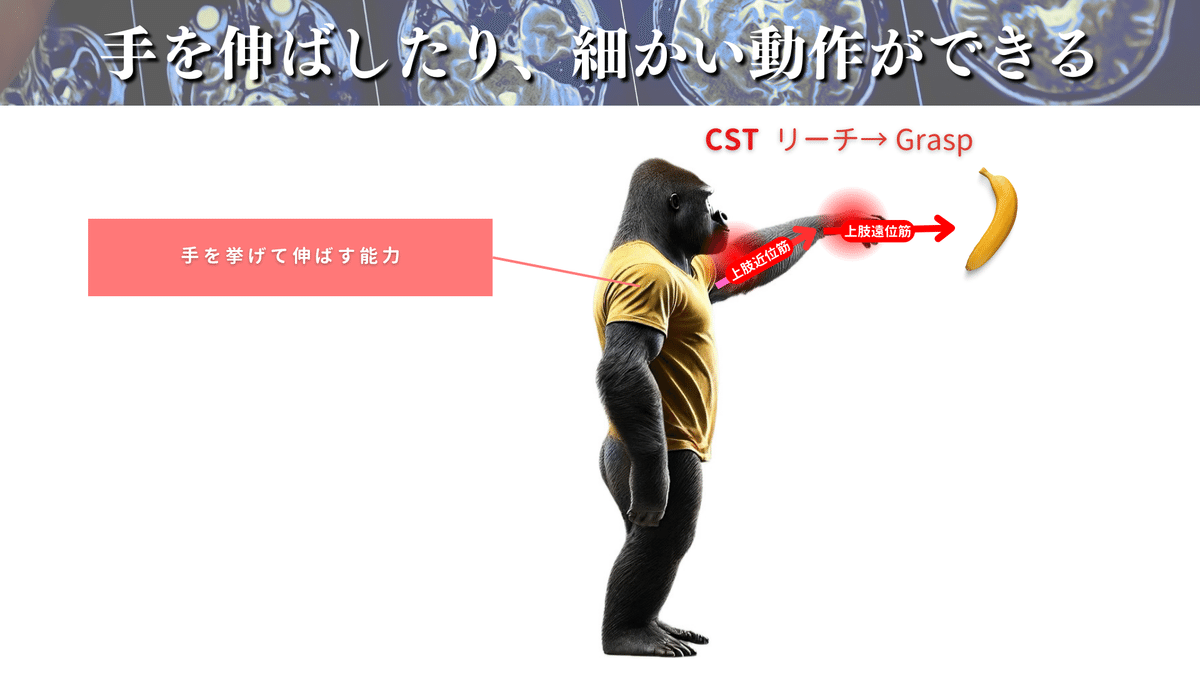

さて、もう少し機能についてお話しをすると、CSTは主に脳と反対側の上下肢を制御していて、特に遠位部の制御を担っています🖐️

CSTは外側皮質脊髄路(LCST)と前皮質脊髄路(ACST)に分かれますが、80〜90%がLCSTですので、CST=LCSTという認識でもOKです👌

LCSTは特に上肢・手指との関連性が強く、LCSTの55%は頸髄レベルに終止すると言われています🖐️

僕たちが行う、手を挙げる動作(バナナをとるなど)や細かな動作(例えばスマホの操作や箸の操作など)はLCSTが大活躍しているわけですね🍌